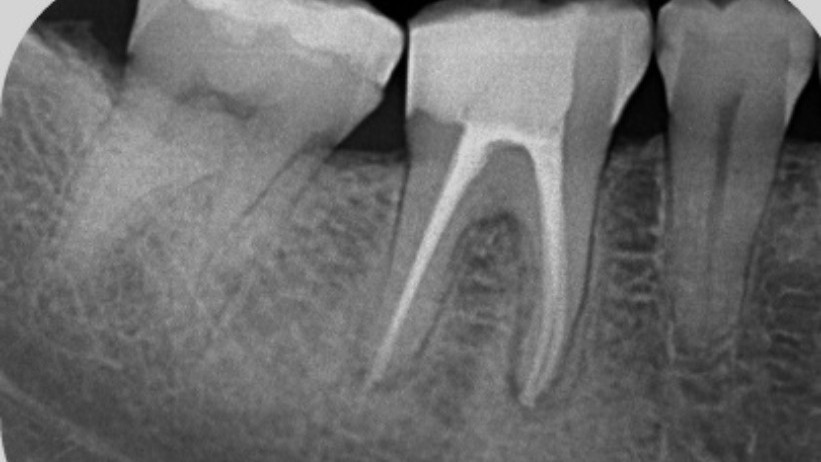

Root Canal Treatment (RCT) is a dental procedure used to treat infection or damage within the tooth while preserving its natural structure. The treatment involves removing the infected pulp, thoroughly cleaning and disinfecting the root canals, and sealing the tooth to prevent future infection. With modern techniques and anesthesia, RCT is a safe and comfortable procedure that effectively relieves pain and restores tooth function. Dr. Ankita is known for her precise, gentle approach to RCT, focusing on pain-free treatment, accuracy, and long-term success, helping patients regain confidence in their smile and oral health.